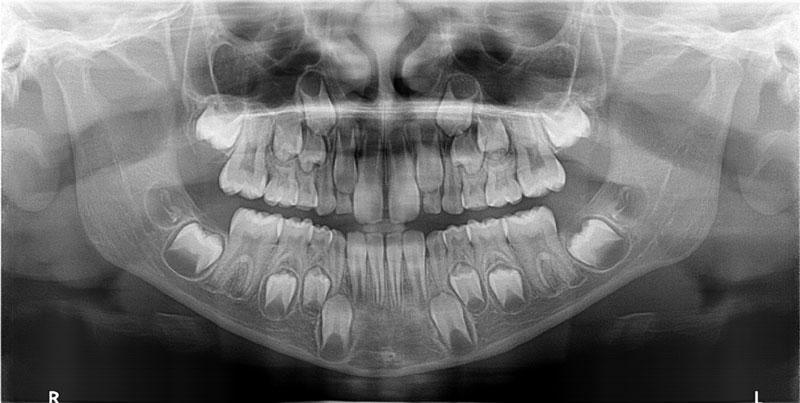

Questa immagine di seguito, mostra una immagine bidimensionale acquisita con un apparecchio tradizionale 2D.